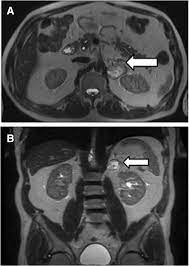

How will you get the test results? The mri of the abdomen will take approximately 60 minutes. What does the procedure involve? In some cases, it may take up to about 2 hours. Abdominal mris are used for a variety of reasons, such as examining:

The images of your scan will be examined by a radiologist and the results will be sent to your referring physician who will review the results with you. A radiologist will examine the images and send a report to your doctor. A complete scan, depending on the sequences performed, and need for contrast enhancement may take 1 hour or more. But the magnet is very powerful. Most pelvis mri exams are done in the main hospital, acc or placer clinics.

How long to wait after mri? How long does it take to get mri scan results? Most pelvis mri exams are done in the main hospital, acc or placer clinics. What are the risks of an mri of the abdomen? The mri of the abdomen will take approximately 60 minutes. What does the procedure involve? In some cases, it may take up to about 2 hours. Jul 08, 2017 · preliminary results from an abdominal mri may come within a few days, but comprehensive results can take a week or more.